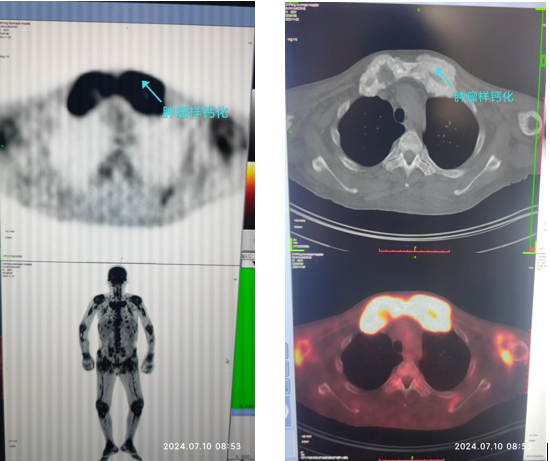

常见的骨痛患者多数见于骨科,给与常规保守或手术治疗。但对于刘叔这样血液透析多年的患者,MDT团队给与了个体化诊疗,结合刘叔的化验,认为刘叔的骨痛根源可能与血液透析并发症有关,随即为患者安排了相关的检查,其中PET-CT提示:全身骨骼骨质密度不均匀增高或减低并多个大小不等囊状影,部分骨、软骨或骨关节周围“肿瘤样钙化”伴代谢不同程度增高,结合病史,考虑代谢性骨病骨及骨关节改变可能。“肿瘤样钙化”、“异常的血钙血磷”、“异常的PTH”,提示刘叔的骨痛可能与CKD-MBD有关,经MDT团队协作会诊,最后诊断为慢性肾脏病CKD5期、血液透析、肾性贫血、慢性肾脏病-矿物质和骨异常(CKD-MBD)、高磷血症、高钙血症、尿毒症肿瘤样钙化性沉积症、不安腿综合征、低蛋白血症、蛋白质-能量失衡。